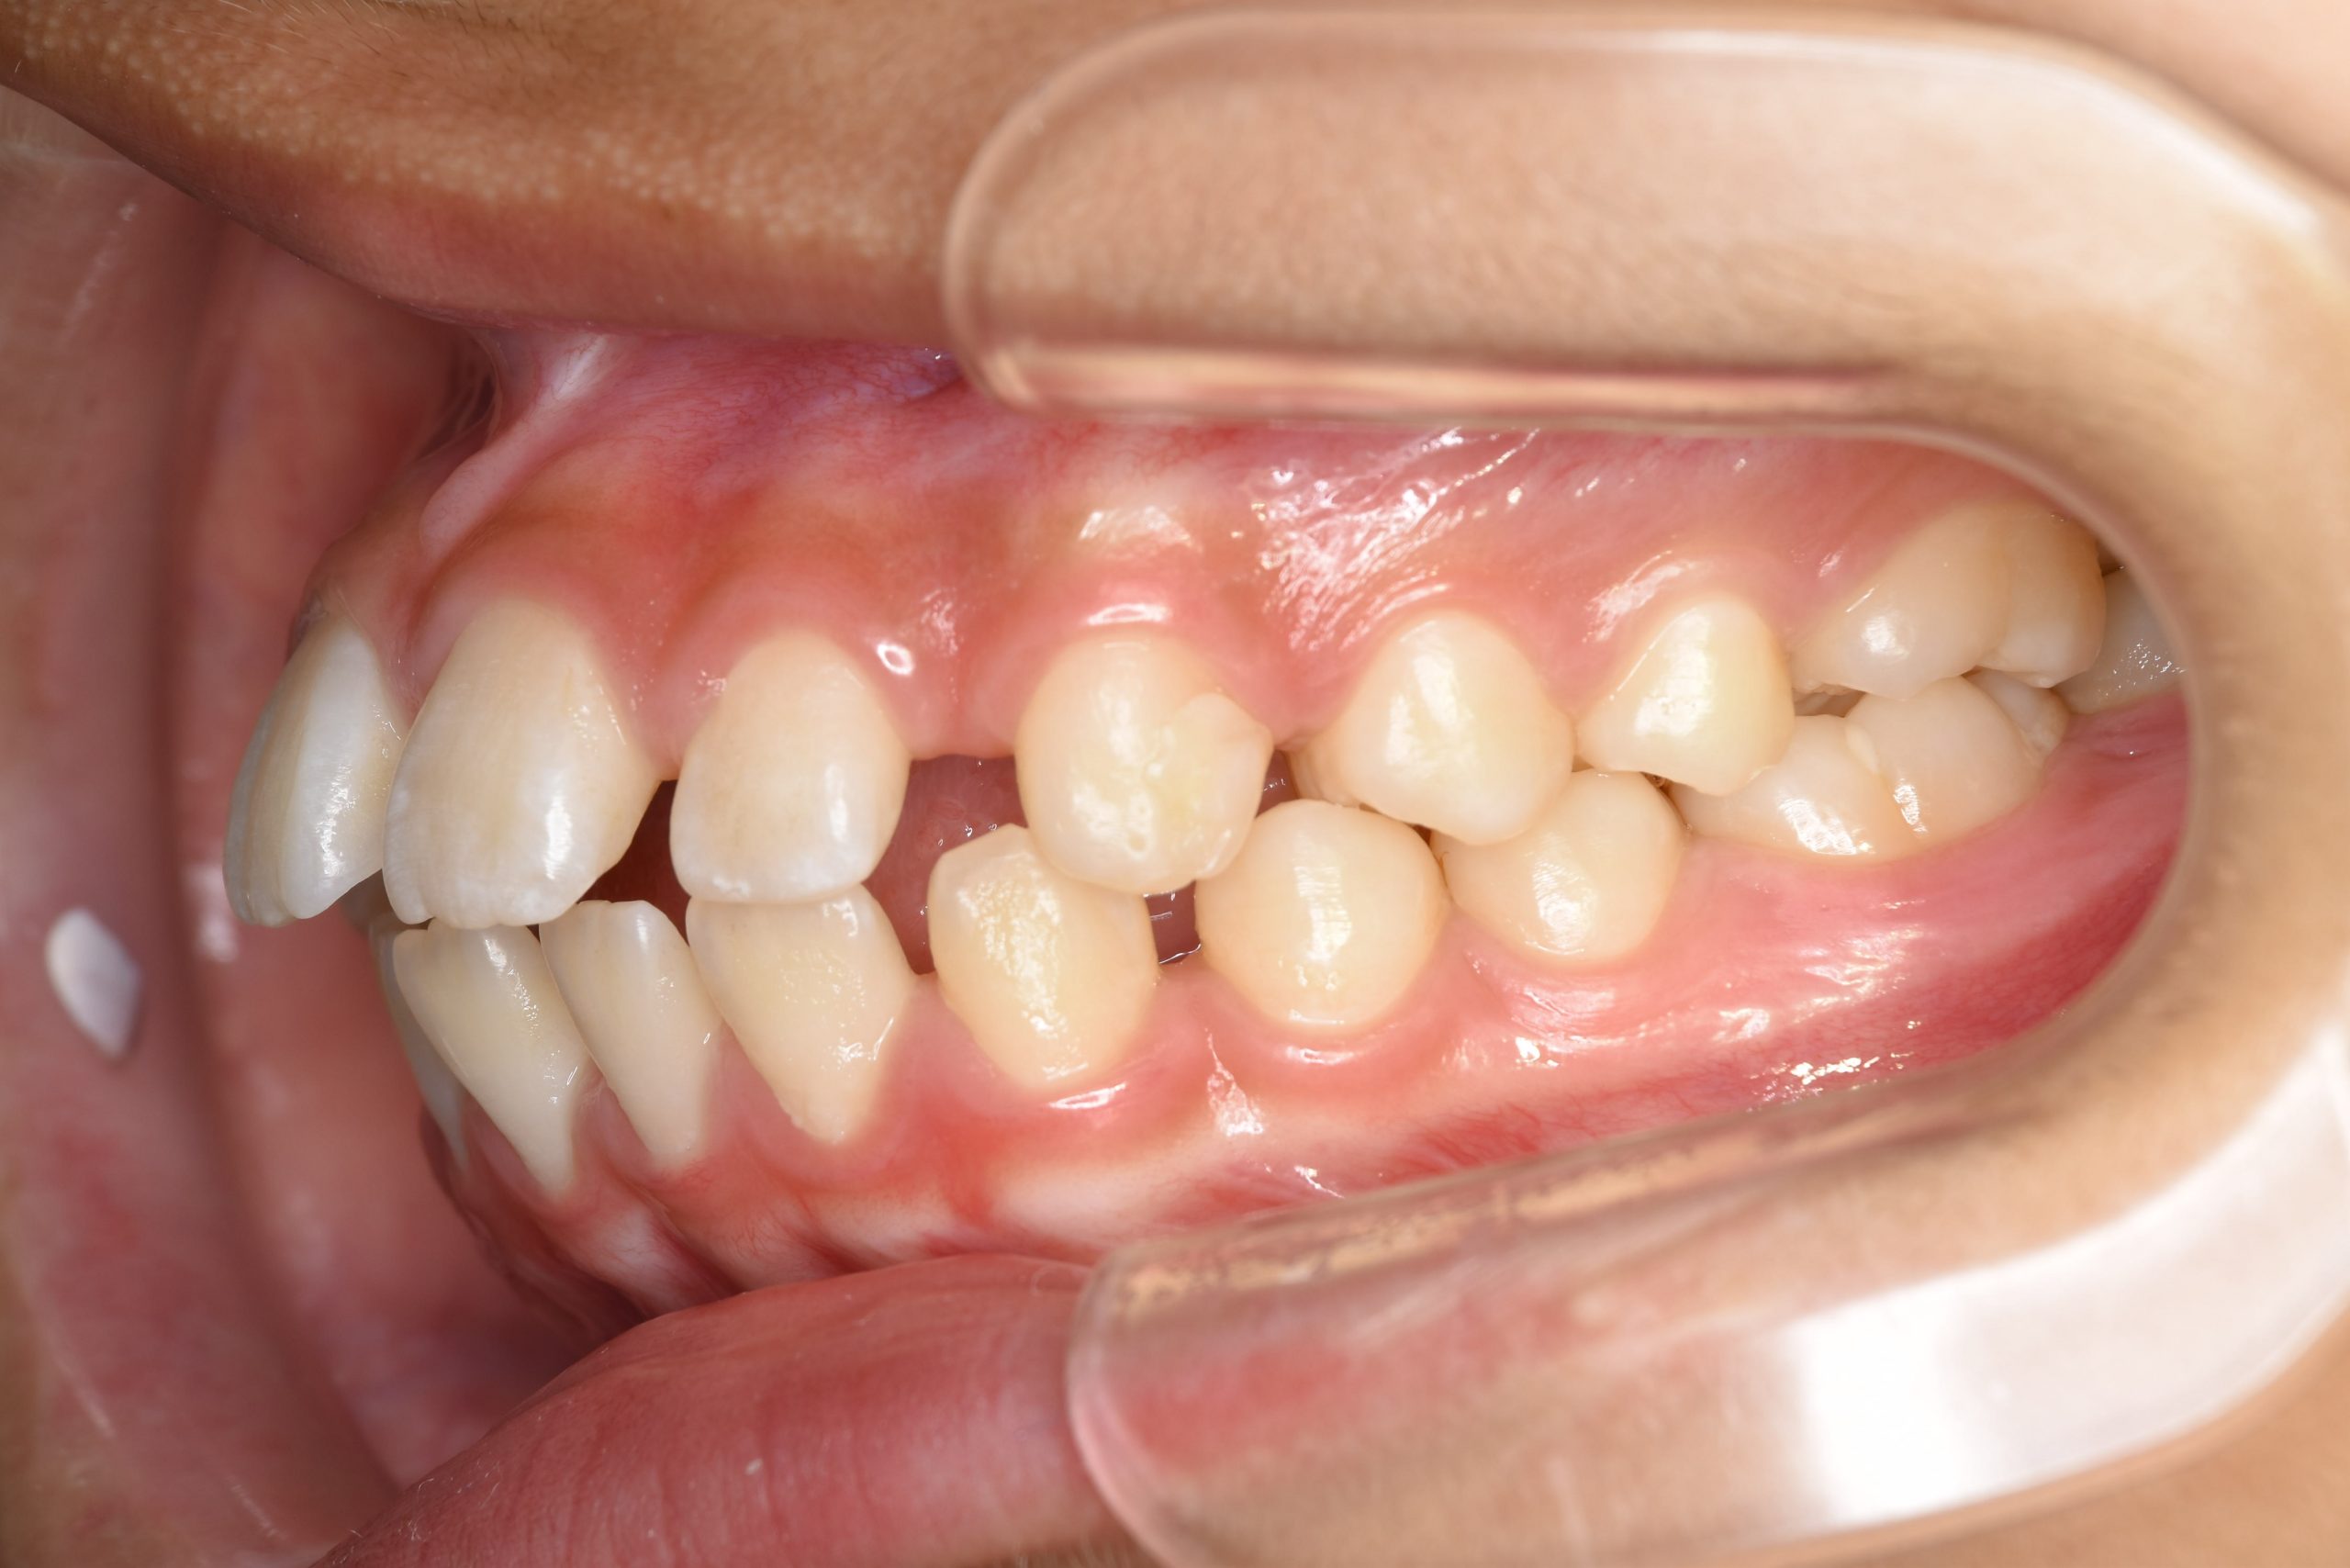

ビフォー

ワイヤー矯正治療|症例_681

主訴 上前歯が出ている|よく口が開いている

施術内容 上顎急速拡大装置と下顎リンガルアーチを用いて上下顎骨を拡大した。

その後マルチブラケット装置を用いて

非抜歯で歯牙を配列し良好な咬合を獲得した。

鼻閉症状は改善した。

治癒期間 2年10か月間